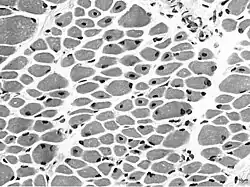

| Muscle biopsy from the quadriceps taken at 3 months of age from a girl with X-linked centronuclear ("myotubular") myopathy due to a mutation in the myotubularin (MTM1) gene and extremely skewed X-inactivation (H&E stain, transverse section). Note marked variability in fibre size, moderate increase in connective tissue and numerous central nuclei. | |

Centronuclear myopathy manifests on muscle biopsy as centrally located nuclei encircled by a perinuclear halo filled with aggregates of glycogen and mitochondria but without myofilaments.[10] All muscles, including extra-ocular muscles, have the distinctive central nucleus,[11] which can affect up to 90% of the fibers.[12]